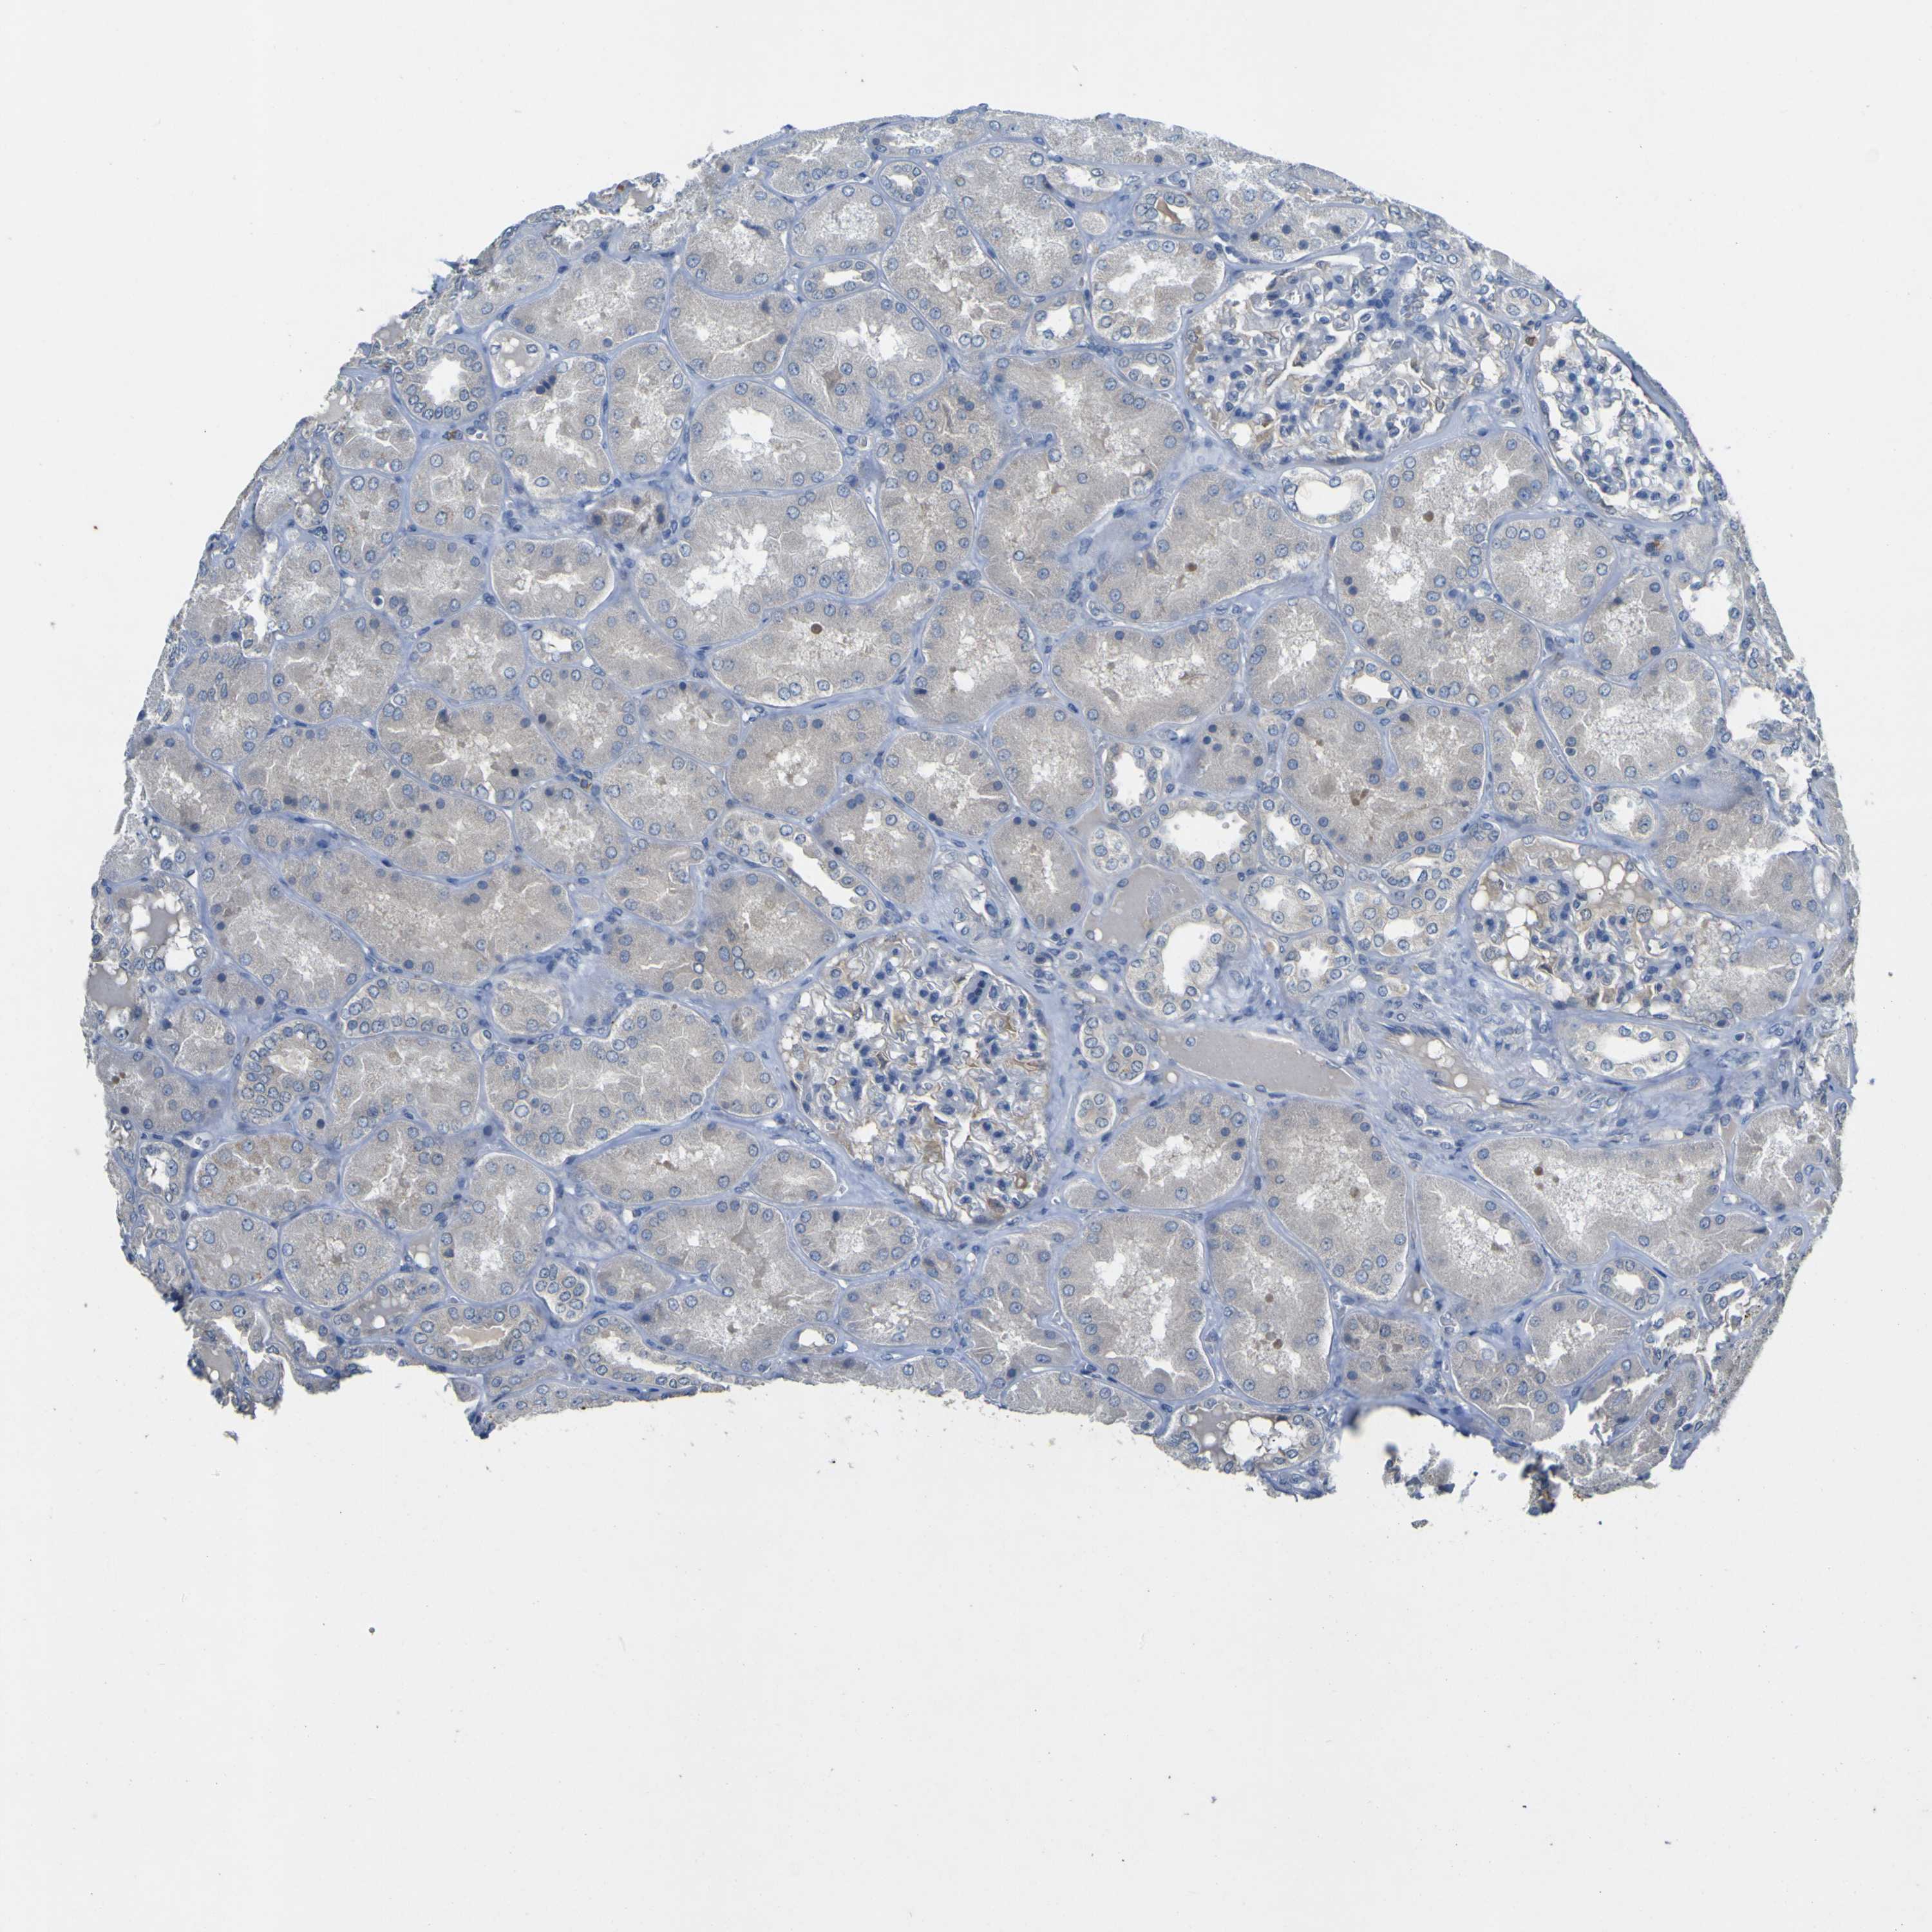

Tissue expression of LDLR Staining in kidney The Human Protein Atlas Protein Atlas Ldlr  Cytoplasmic expression in a subset of cells including cells in the gastrointestinal tract, leydig. The pathology section contains mrna and protein expression data from 17 different forms of human cancer. Correlation analysis based on mrna. The structure section provides predicted structures from the alphafold protein structure database and includes. Protein structure for human protein ldlr (ldlcq2) we use cookies to. Protein Atlas Ldlr.

From www.proteinatlas.org